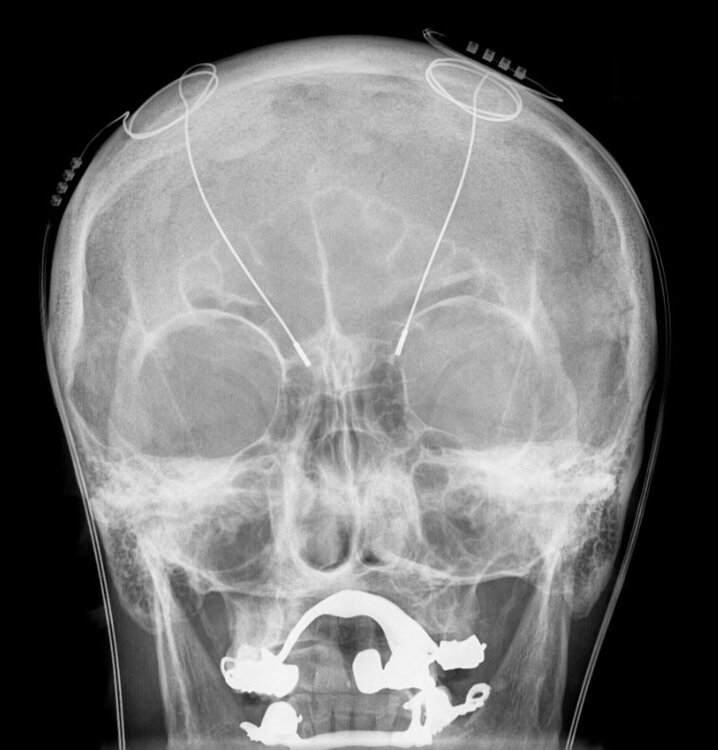

Au milieu des années 80, Pierre Pollak, le neurologue et Alim Louis Benabid, le neurochirurgien, découvrent la possibilité de traiter le tremblement par la stimulation d'un noyau spécifique (le Vim) du thalamus, une structure profonde du cerveau.

A la même époque, des travaux fondamentaux, issue notamment du développement de nouveaux modèles de Parkinson chez le primate (les modèles "MPTP"), conduisent à considérer qu'une partie importante des symptômes de la maladie de Parkinson est liée à une activité excessive du noyau sous-thalamique, une structure de petite taille située, comme son nom l'indique, sous le thalamus.

Sur la base de ce qu'ils ont observé sur le tremblement, et qui suggérait que la neurostimulation à haute fréquence reproduisait les effets d'une lésion, Pollak et Benabid vont traiter les premiers patients parkinsoniens par stimulation du noyau sous-thalamique au début des années 90 à Grenoble. Les améliorations très spectaculaires qui seront observées vont rapidement convaincre la communauté neurologique mondiale de l'intérêt majeur de cette approche thérapeutique, lorsque le traitement médical ne suffit plus à maintenir la qualité de vie du sujet.